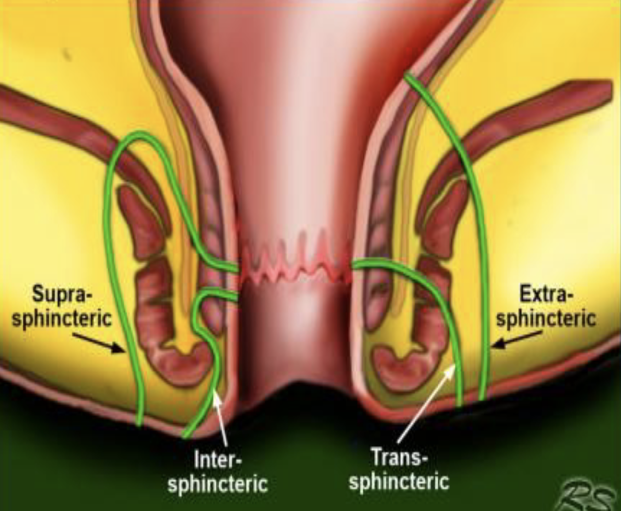

Classification des Fistules

Fistule

Exemple: Fistule intersphincterienne a 6H

Exemple: Fistule trans-sphincterienne à 6h

Exemple: Fistule trans-sphincterienne 11h